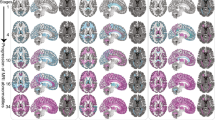

Standardized brain MRI protocol

Brain MRI is important for achieving a prompt, accurate diagnosis of MS, because of its high sensitivity for detecting white matter plaques (Figure 1). However, several factors related to MRI examination—including patient positioning, the choice of pulse sequences and pulse-timing parameters, spatial resolution, coil technology, contrast medium, and magnetic field strength—have a major influence on lesion detection.76 Various guidelines have consistently recommended a standardized brain MRI protocol (Box 2).77,78,79,80,81 This approach consists of multisequence MRI performed at a magnetic field strength of at least 1.5 T (preferably 3.0 T) with a maximum slice thickness of 3 mm and an in-plane spatial resolution of 1 × 1 mm (voxel size 3 × 1 × 1 mm), and using the pulse sequences described in Box 2. In addition, the protocol should be completed in 25–30 min.

a | Pre-contrast, b | axial T1-weighted and c | dual-echo T2-weighted sequences, followed by d | contrast-enhanced sagittal, e | axial 2D T2-weighted fluid-attenuated inversion recovery (FLAIR) and f | axial T1-weighted sequences. With this strategy, there is no penalty in terms of total acquisition time, and it ensures a minimum delay of 5 min between gadolinium injection and acquisition of the T1-weighted sequence.